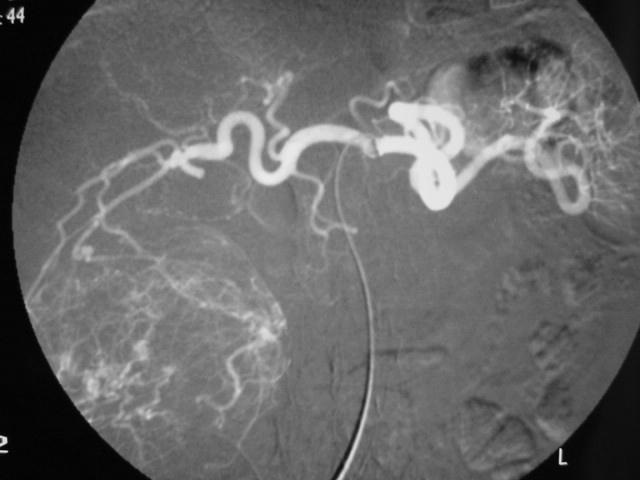

在没有出现多排CT之前,在肝癌肝动脉栓塞之前首先应该进行腹腔动脉造影以及肠系膜上动脉造影,以判定肝脏血管解剖和门脉血流以及是否存在胃底食道血管曲张。然后再行肝总动脉或肝固有动脉造影,以确定肿瘤的范围并辨认供血动脉。如果必要,肝动脉造影还应取斜位。如今多排CT的普遍应用可以更轻易获取肝动脉解剖变异,肝癌供血以及门静脉受累情况,是否可以直接进行肝癌主要供血动脉的栓塞应直接到考虑。

多排CT血管重建还可以发现位于肝表面肿瘤或者肝动脉存在狭窄或闭塞的情况下,是否有膈下动脉、肋间动脉或其它侧支动脉肿瘤供血。

判断肿瘤供血主要决定需要栓塞的肿瘤血管。如果肿瘤的范围较大,则应从肝固有动脉或者右肝、左肝动脉进行化疗性栓塞。如果将导管置于肝固有动脉有一定的困难,或可先进行胃十二指肠动脉栓塞(通常为弹簧栓子)以改变血流方向,从而可以从肝总动脉处释放栓塞剂。这项技术也用于左肝动脉从胃左动脉发出处。当导管不能被放入发自胃左动脉的副左肝动脉远端时,这项技术也是有效的。如果肝固有动脉严重的狭窄或者闭赛,则可以使用球囊导管经门静脉周围的动脉侧支阻塞肝总动脉从而达到肿瘤的化学栓塞作用。